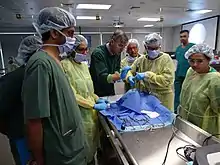

Endoscopic sinus surgery, advocated and popularized by Professor Stammberger, is often very effective for most people, providing rapid symptom relief. Endoscopic sinus surgery is minimally-invasive and is done entirely through the nostril with the help of a camera. Surgery should be considered for those with complete nasal obstruction, uncontrolled runny nose, nasal deformity caused by polyps or continued symptoms despite medical management.[7] Surgery serves to remove the polyps as well as the surrounding inflamed mucosa, open obstructed nasal passages, and clear the sinuses. This not only removes the obstruction caused by the polyps themselves, but allows medications such as saline irrigations and topical steroids to become more effective.[18] It has been suggested that one of the main objectives in sinus surgery for polyps is to allow delivery of the steroids into those areas of the sinuses where polyps develop, namely, the ethmoid sinuses. Specially designed long nozzles had been developed to use postoperatively to deliver steroids into those areas after sinus surgery for polyps.[19]

Surgery lasts approximately 45 to 60 minutes and can be done under general or local anesthesia.[18] Most people tolerate the surgery without much pain, though this can vary from person to person. The person should expect some discomfort, congestion, and drainage from the nose in the first few days after surgery, but this should be mild.[20] Complications from endoscopic sinus surgery are rare, but can include bleeding and damage to other structures in the area including the eye or brain.[20]

Many physicians recommend a course of oral steroids prior to surgery to reduce mucosal inflammation, decrease bleeding during surgery, and help with visualization of the polyps.[12] Nasal steroid sprays should be used preventatively after surgery to delay or prevent recurrence.[7] People often have recurrence of polyps even following surgery. Therefore, continued follow up with a combination of medical and surgical management is preferred for the treatment of nasal polyps.[12]